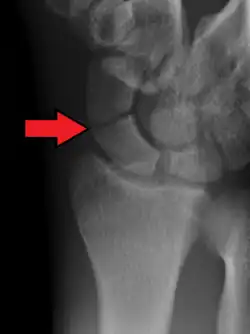

Le diagnostic de fracture est difficile à réaliser car les lésions éventuelles peuvent ne pas être immédiatement visibles sur les radiographies standard du poignet de face et de profil. On pratique aussi une radiographie avec incidences spéciales (inclinaison de 30° vers le coude) qui permettent de dérouler l'os et ainsi de visualiser plus précisément le trait de fracture[5].

A : distale (20% des cas)

B : centrale (60%)

C : proximale (20%).